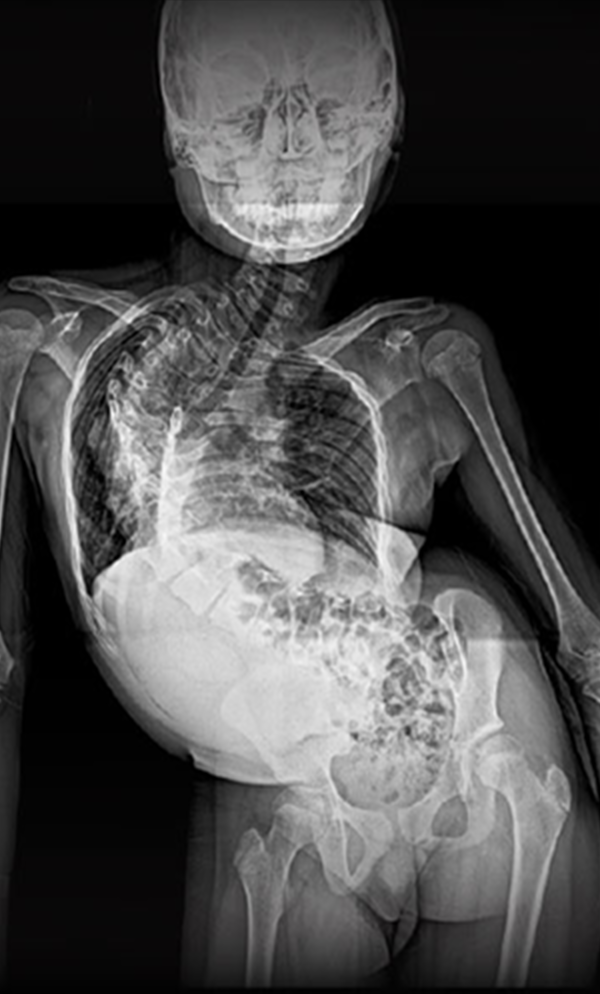

BEYOND RECOVERY : REAL STORIES

Gallery : Before - After